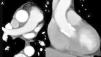

Contrast thoracic computed tomography images: (A) aortic dissection with the intimal tear dividing the aorta into a true lumen, fully contrasted, and a false lumen, only slightly contrasted (arrow); (B) coronal plane reconstruction similar to the aortography view showing the slightly contrasted false lumen (arrow), corresponding to the subtraction image on aortography (Figure 1B).